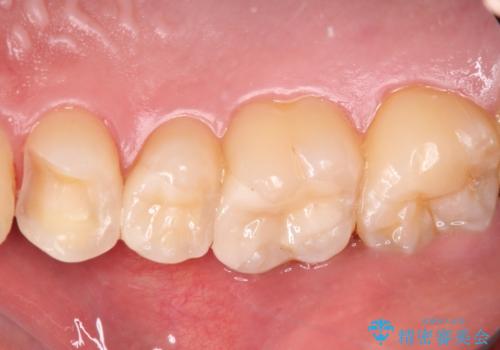

詰め物が外れた セラミックインレー修復

- 以前治療した詰め物が外れてしまい、冷たいものがしみることを主訴として来院された患者様です。

むし歯がないことを確認し、セラミックインレーにて修復するととしました。

適合の良いセラミックインレーの装着により、冷たいものがしみる症状はなくなりました。